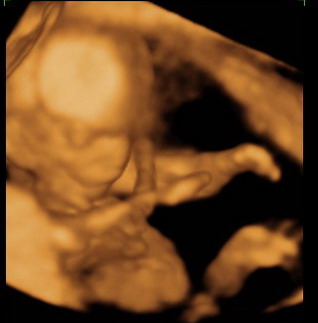

Gratula a kukishoz! Úgy tűnik minden Kisfiúnak ez a szokása! Apa akkor nagyon büszke :lol: :lol: ! Rajta múlt :D ! Kép KUKAC

Kép levitáció Kép Orr+fülfogás

Kép BOX

Kép Lúdtalp nincs :):)lábfej torna Kép Kép Álmos vagyok

Kép guggolás Kép Tipikus pasi-láb között matatás

Kép Nyújtózás

Kép Hello Kép Elég volt, most már alszom

Nagyon édi a kukacos, és pont úgy mutatta meg, mint a miénk :wink: :D ! Nekem csak ez a képem van a tegnapiról,, mert az egészet megkaptuk DVD-n, így képet csak a "bizonyítékról" kaptunk :D ! Viszont a DVD nagyon szuper, tényleg annyira virgonc volt, hogy hihetetlen, a szívhangját alig lehetett elcsípni, mert ellándóan elficánkolt! Nekem a kedvencem az a rész, mikor hosszan szopizza az úját, csücsörítget, és közben nyel a magzatvíből is, annyira cuki :D :D :D !!!!